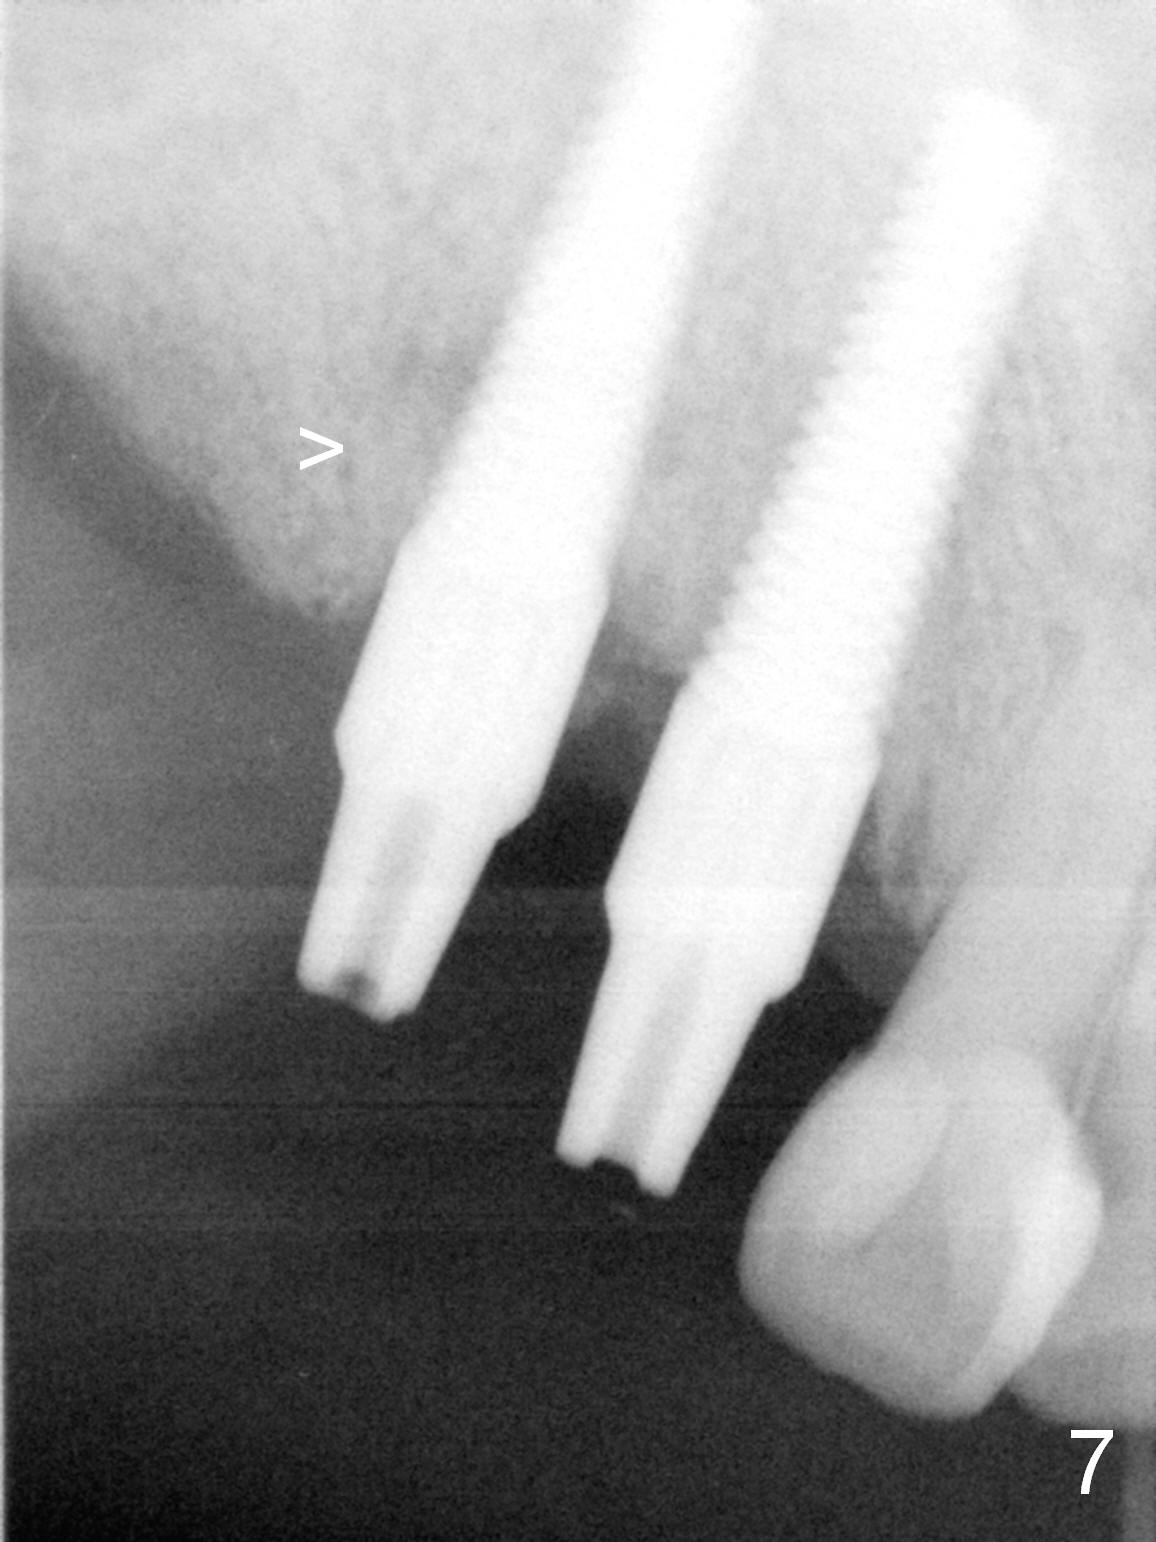

Several of CK's upper teeth (apparently in cross bite) are to be restored with implants (Fig.1).  The first two are #5 and 6; note the oval roots (Fig.2).  After extraction, and curettage, osteotomy starts in the palatal aspect of each socket.  The 1st intraop PA shows that the trajectory at #6 is incorrect (Fig.3).  After adjustment, osteotomies look parallel (Fig.4: D: 3.5x20 mm drill; T: 4.5x20 mm tap).  This suggests how important it is to use parallel pins to check initial osteotomies for neighboring implants (Fig.3).  The trajectory of the implants remains acceptable (Fig.5: 4.5x20 mm with insertion torque »60 Ncm); so is the position of the implants (as palatal as possible; Fig.6 (*: bone graft)).   Immediate provisionals are fabricated in cross bite.

Bone density in the distal gap of #5 appears to have increased 3 months postop (Fig.7).  Prior to definitive restoration cementation (3.5 months postop), the buccal plate does not collapse (Fig.8).  There is no occlusal contact of the new restorations (Fig.9 *), probably due to bite discrepancy (Fig.10,11).